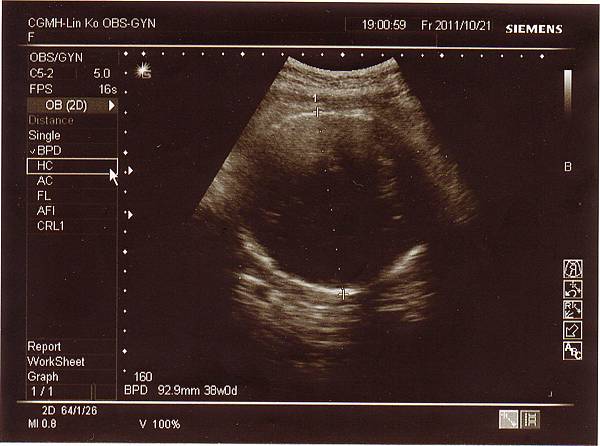

一開始產檢時,醫生量了頭圍結果約38週,也就是大了一周左右,

後來又換了角度量小了一些,但仍是正常範圍,

妹妹的體重來到2700多克,比上次多了一百克左右(還好有長大),